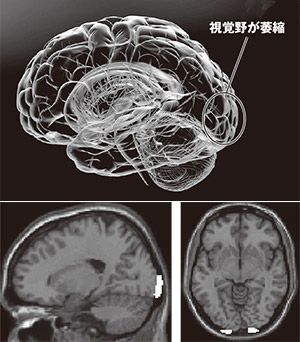

DV目撃でなぜ視覚野は萎縮するのか

わたしがハーバード大学との共同で行った研究によると、子ども時代にDVを目撃して育った人は、脳の「視覚野」の一部で、夢や単語の認知などに関係した「舌状回(ぜつじょうかい)」と呼ばれる部分の容積が、正常な脳と比べ、平均しておよそ6%萎縮していた。これは無意識下の適応とも考えられる。つまり、生き延びるために、脳はその形を自ら変えるのだ。視覚野が萎縮すると会話をする相手の表情が読み取れなくなり、コミュニケーションをとるさいに支障が出てしまう。子どもにとって大問題だ。